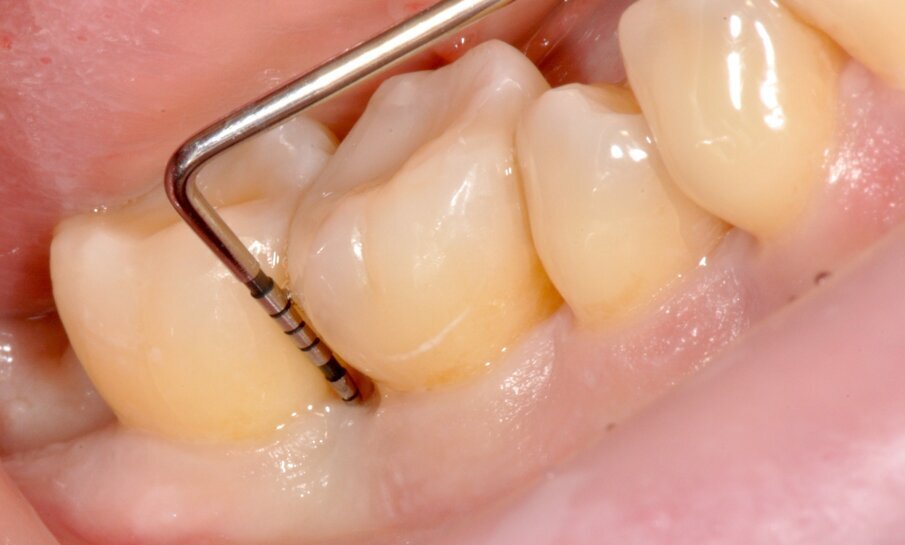

Fig. 4 - Sondaggio DV dell’elemento 4.6 di 9 mm.

Fig. 7 - Disegno del lembo con preservazione della papilla interdentale.

Tuttavia, nei siti DV e MV degli elementi 4.6. e 4.7 si riscontra nuovamente BOP e SOP positivo. Si decide dunque di effettuare un intervento di chirurgia ricostruttiva, finalizzato alla chiusura del difetto intra-osseo e programmato ad una settimana dalla seduta di richiamo di igiene orale professionale (GBT®). Dopo uno sciacquo per 60 secondi con collutorio a base di Clorexidina 0.12% e Cloruro di Cetilpiridinio (Paroex® GUM®), si esegue anestesia locale plessica con Articaina 4% con adrenalina 1:100.000 e disegno di un lembo M-MIST (Modified-Micro Invasive Surgical Technique)5. La scelta di questo tipo di lembo è volta alla massima preservazione della vascolarizzazione del sito chirurgico e al mantenimento della papilla interdentale.